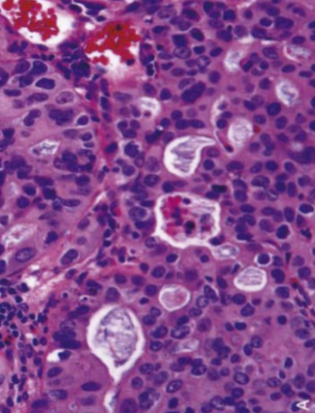

Eosinophilic Esophagitis

eosinophilic microabscesses

Morphology: large numbers of eosinophils or eosinophilic microabscesses in epithelium